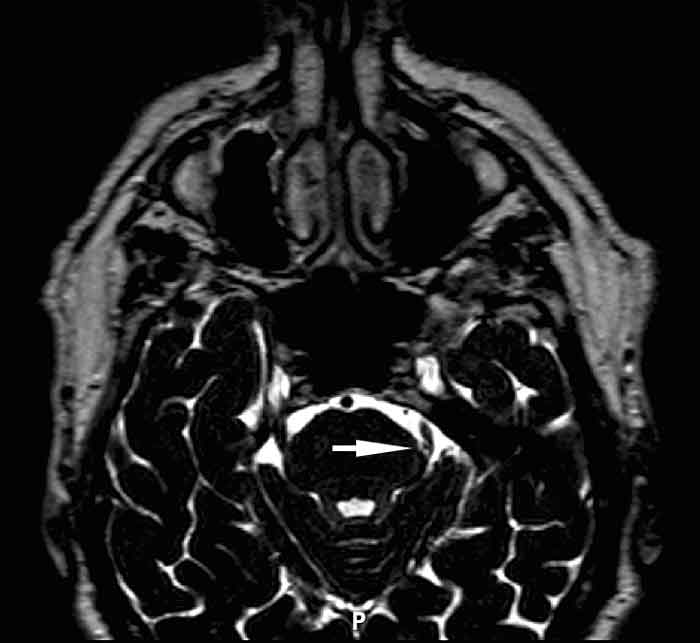

Om neurologiska statusfynd noteras, ska undersökning med MRT göras för att utreda om det finns en bakomliggande patologi. Även i fall utan statusfynd rekommenderas MRT-undersökning hos yngre patienter eller när man inte får ett prompt svar på farmakologisk behandling, eftersom man funnit bakomliggande patologi hos upp till 15 procent [5] av patienter utan andra symtom än smärta. MRT-undersökning är också viktig inför en diskussion om kirurgisk behandling, för att utröna huruvida något kärl trycker på nerven. För att se både nerv och kärl ska MRT-undersökningen omfatta en extremt T2-viktad sekvens (CISS [constructive interference in steady state] eller DRIVE [driven equilibrium) med tunna snitt över pons och mesencefalon.

Magnetresonanstomografi med extremt T2-viktad sekvens (DRIVE [driven equilibrium]). På patientens vänstra sida syns arteria cerebelli superior trycka mot trigeminus­nerven vid dess inträde i hjärnstammen (pil).